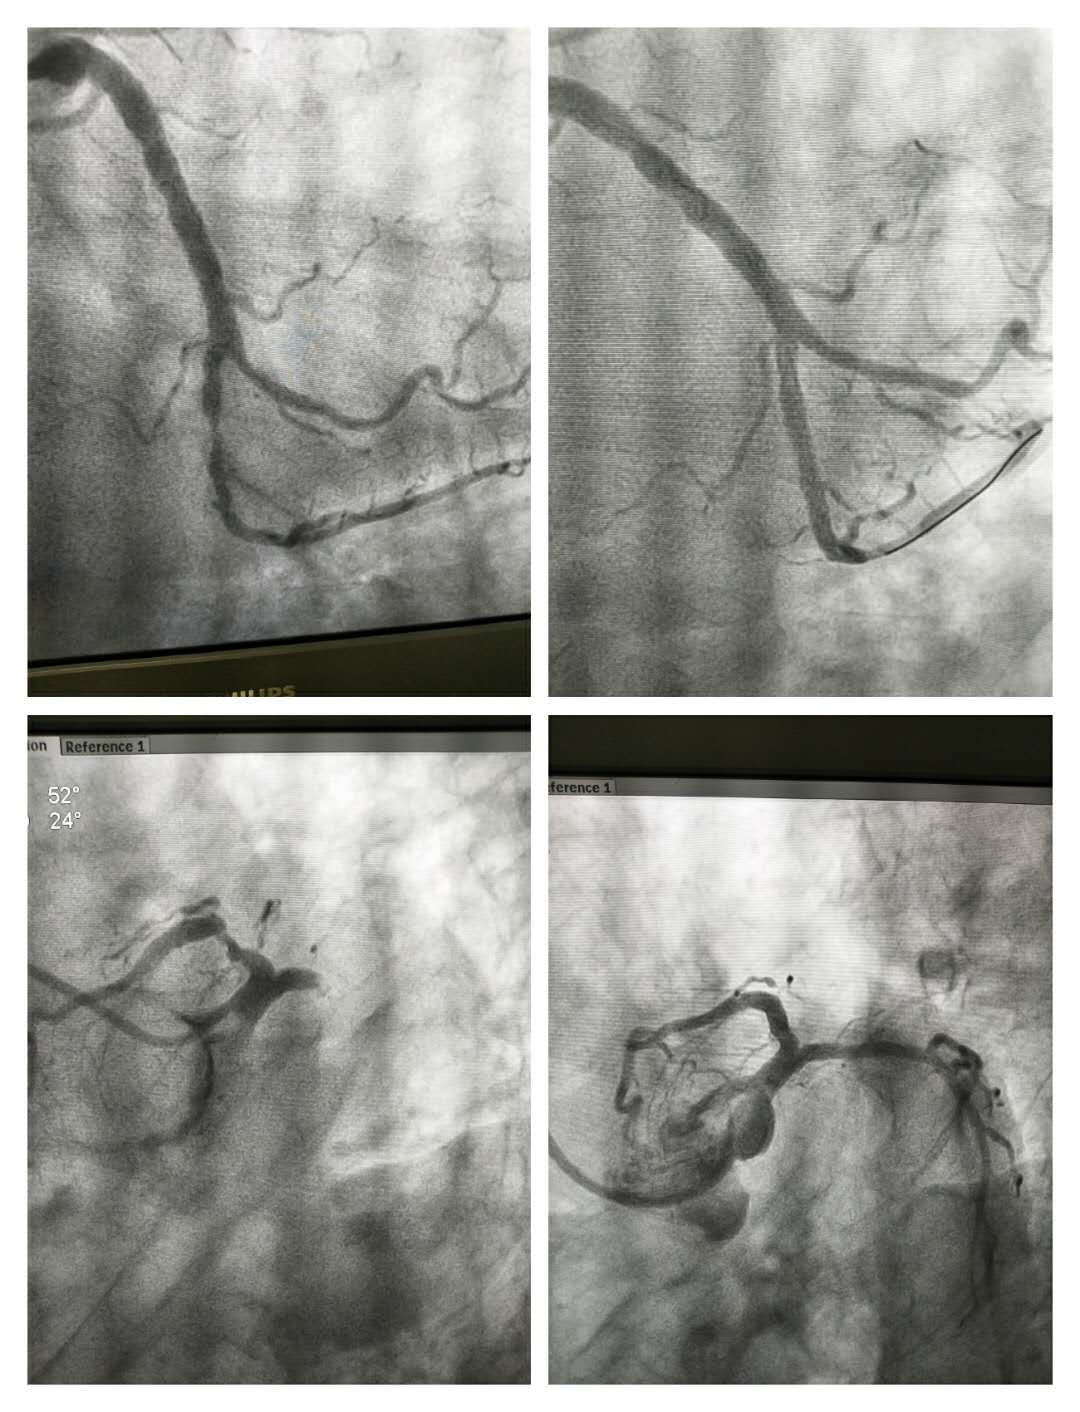

疫情防控期间,心血管病科医护人员坚守岗位,医护人员孙洪然、王法敏、王启霞、陈孝波以备科室业务不时之需,主动以科室为家,随时待命。在严格落实防护措施、保护个人和患者安全的前提下,完美开展急诊PCI两例!患者一句理解的话语、一个鼓励的眼神就是对医护工作最大的肯定。一面锦旗代表的不止感激,更有深深的信赖。